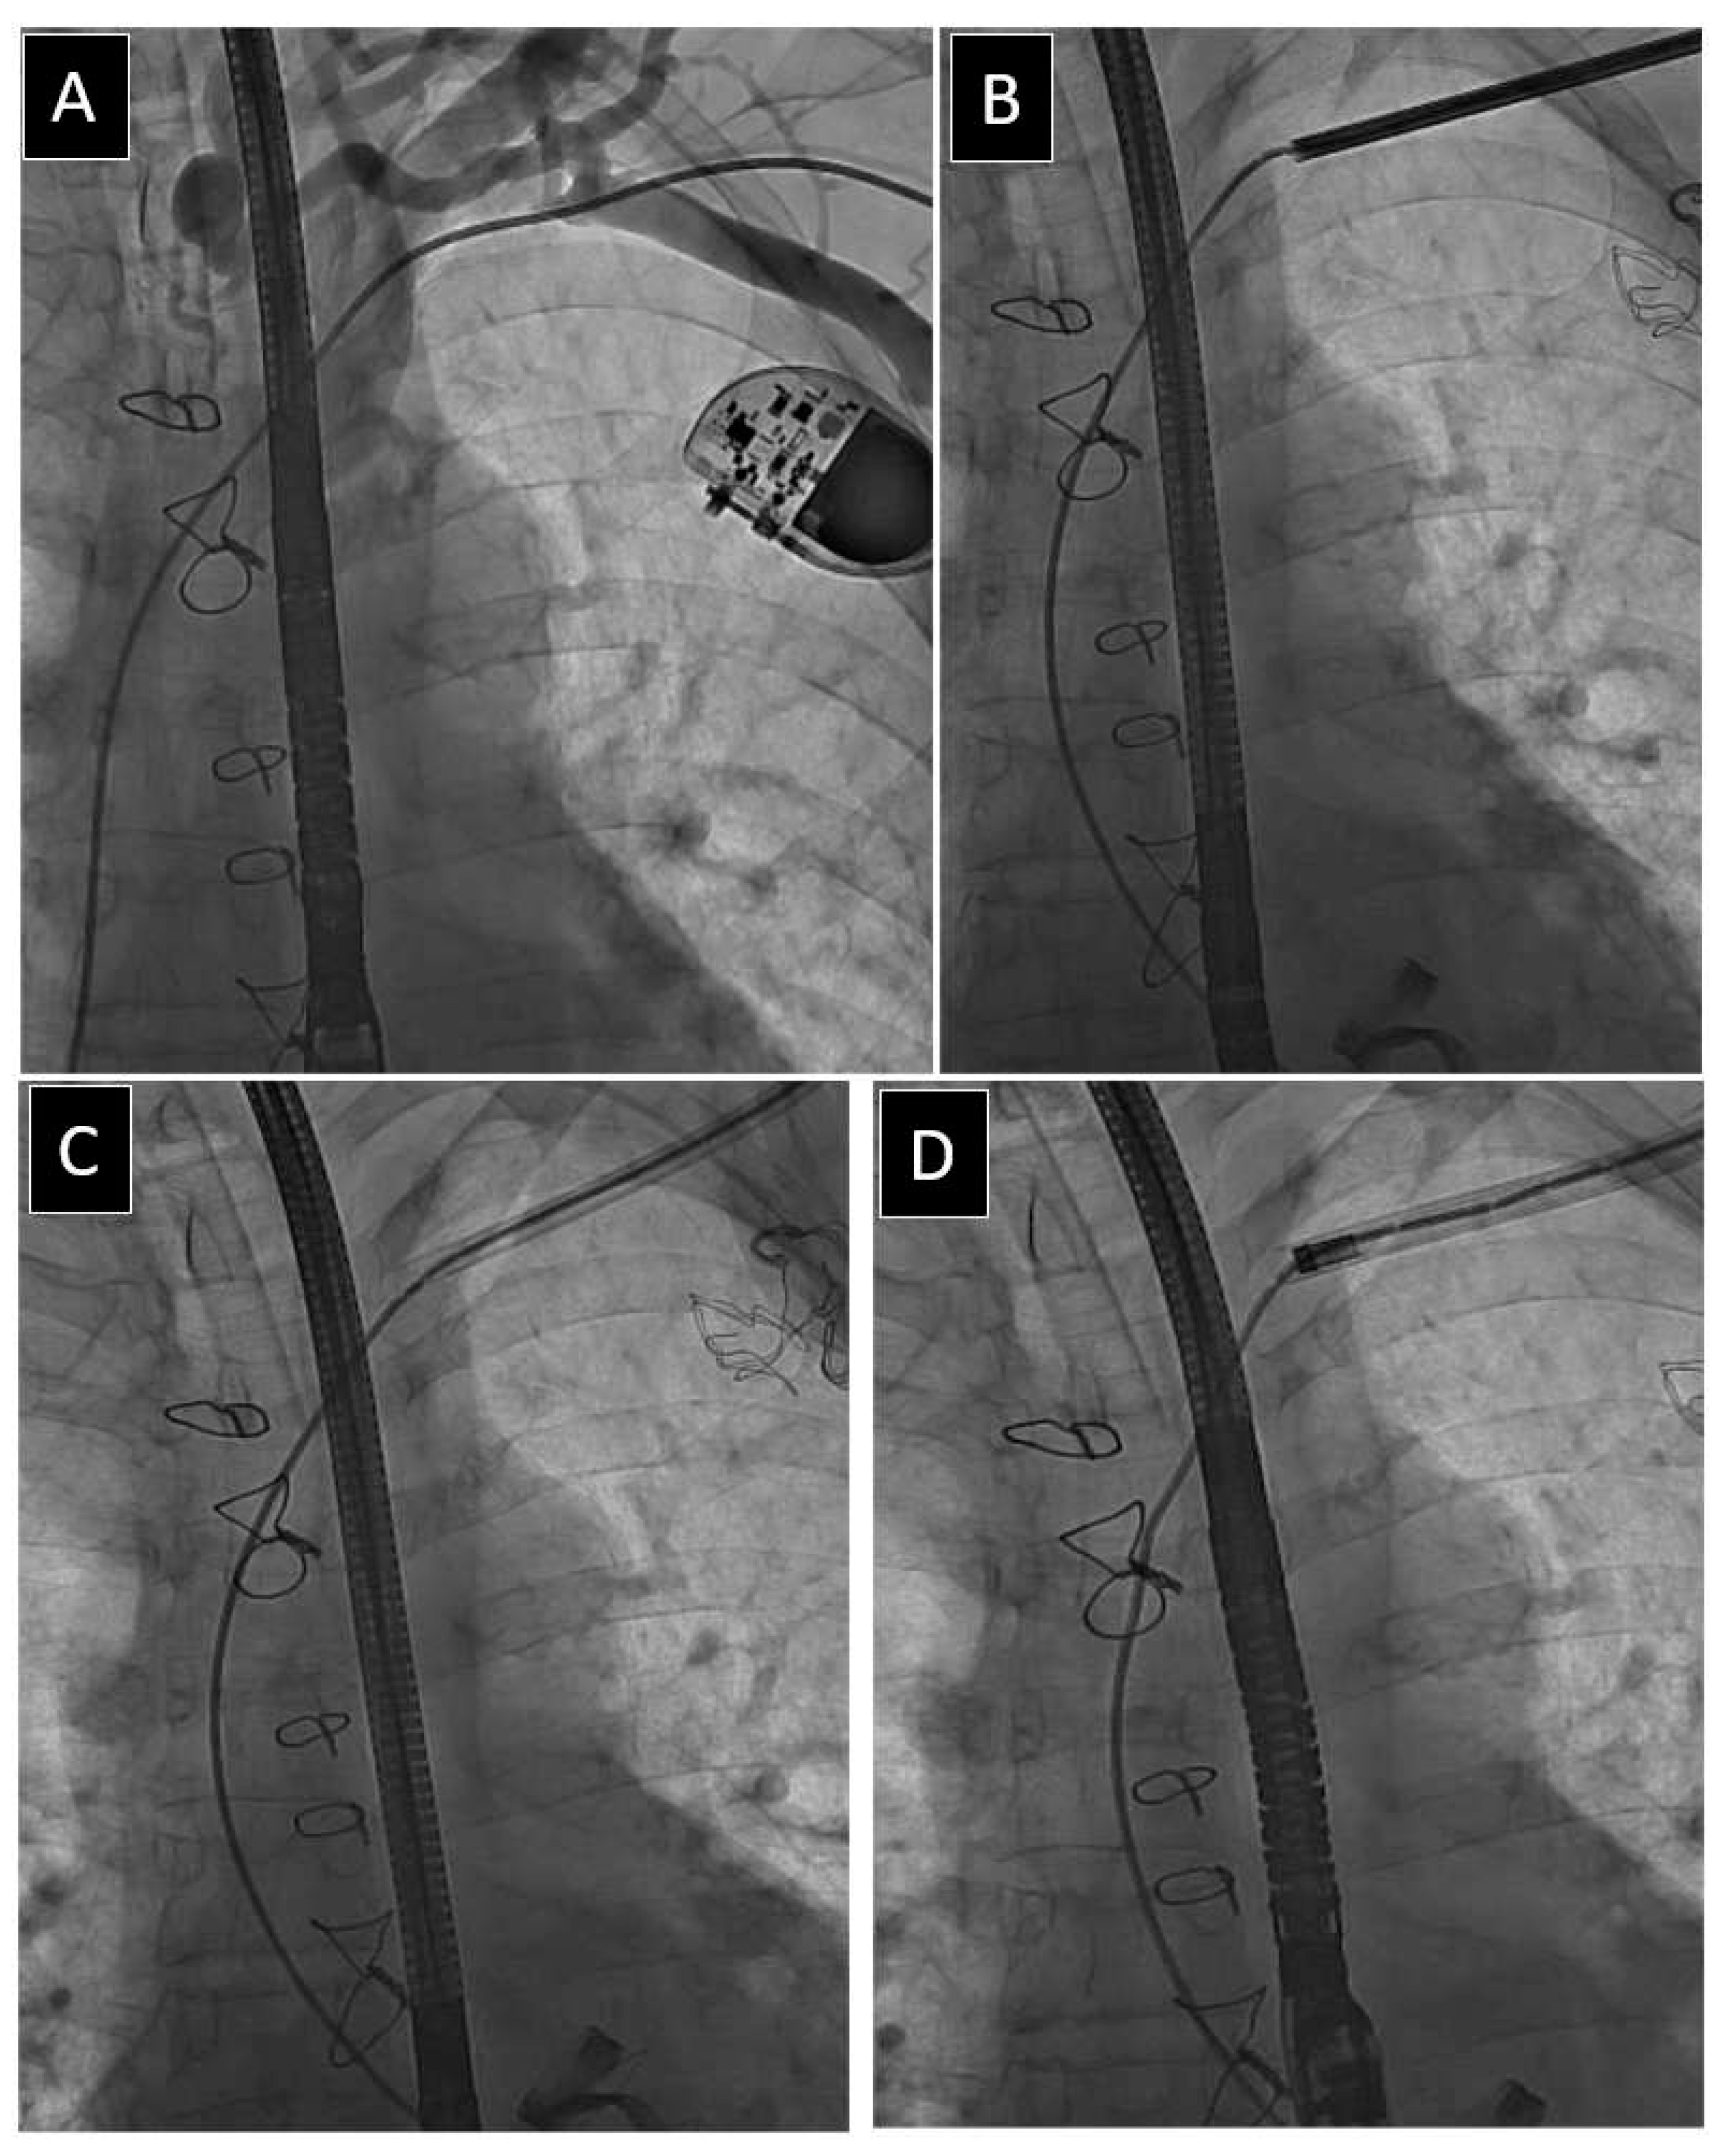

| Blockage in lead implant vein/subclavian region * | 297 (7.98) | 63.41 ± 17.80 p = 0.007 | 51.05 ± 19.12 p = 0.001 | 102 (34.34) p = 0.096 | 171 (57.58) p = 0.719 | 51.45 ± 14.38 p = 0.045 | 4.67 ± 3.92 p = 0.180 | 63 (21.21) p = 0.001 |

| Blockage in lead implant vein/subclavian region * | 297 (7.98) | 2.07 ± 0.81 p = 0.001 | 17 (5.72) p = 0.016 | 47 (15.83) p = 0.004 | 13 (4.38) p = 0.001 | 2.26 ± 1.27 p = 0.001 | 36 (12.12) p = 0.017 | 14 (4.71) p = 0. 206 |

| Blockage in lead implant vein/subclavian region * | 297 (7.98) | 1.86 ± 0.83 p = 0.001 | 52 (17.51) p = 0.001 | 63 (21.21 p = 0.015 | 45 (15.15) p = 0.004 | 205 (69.02) p = 0.013 | 149.3 ± 93.17 p = 0.001 | 22.19 ± 17.75 p = 0.001 |

| Blockage in lead implant vein/subclavian region * | 297 (7.98) | 32.63 ± 36.89 p = 0.001 | 17.26 ± 18.36 p = 0.001 | 22 (7.41) p = 0.001 | 297 (100.0) p = 0.001 | 36 (12.12) p = 0.001 | 4 (1.35) p = 0. 831 |

| Blockage in lead implant vein/subclavian region * | 297 (7.98) | 2.93 ± 4.82 p = 0.001 | 149 (50.17) p = 0.001 | 30.33 ± 22.48 p = 0.001 | 3.15 ± 1.04 p = 0.001 | 14.30 ± 7.92 p = 0.001 | 2.40 ± 0.82 p = 0.001 |

| Blockage in lead implant vein/subclavian region * | 297 (7.98) | 12 (4.04) p = 0.004 | 8 (2.69) p = 0.008 | 0 (0.00) p = 0. 878 | 3 (1.01) p = 0.577 | 6 (2.02) p = 0.433 | 35 (11.79) p = 0.001 |

| Blockage in lead implant vein/subclavian region * | 297 (7.98) | 262 (88.22) p = 0.001 | 0 (0.00) p = 0.465 | 2 (0.67) p = 0.031 | 2 (0.67) p = 0. 346 | 14 (4.71) p = 0.096 | 72 (24.24) p = 0.073 |